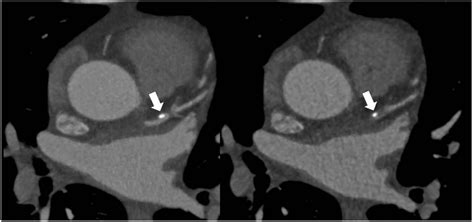

Discrepancies between Coronary Artery Calcium Score and Coronary Artery ...

3276Γ—5534